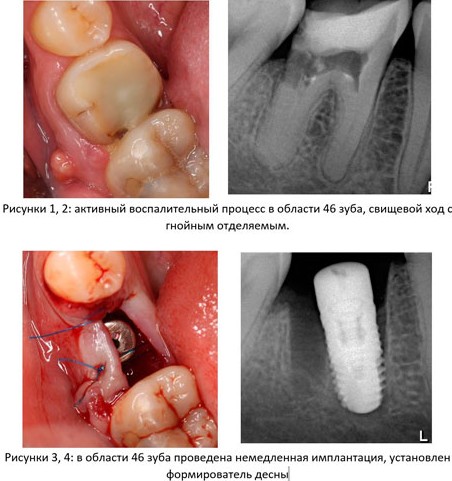

1. Стадия воспалительного процесса. За редким исключением большинство зубов удаляются из-за развитого воспалительного процесса (периодонтита) и невозможности его терапевтического лечения и/или реставрации зуба цивилизованными методами. Ремиссия или хроническое течение заболевания говорит о том, что организм «справляется» с воспалительным очагом – и с этой точки зрения, наличие даже обширного периапикального процесса не является противопоказанием к установке импланта в лунку зуба. И наоборот, обострение периодонтита, болевой синдром, гноетечение и т. п. является противопоказанием к немедленной имплантации.

Это, разумеется, относительно, потому степень риска оценивается в каждом конкретном клиническом случае (рис. 1-4):

Другими словами, до определенных пределов (каких – рассматривается индивидуально) даже острый воспалительный процесс не является абсолютным противопоказанием для операции немедленной имплантации.